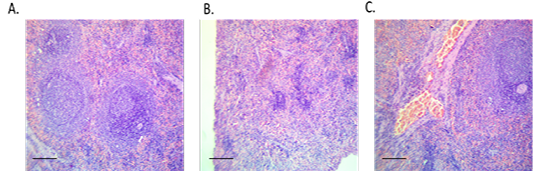

Figure 4

Spleen sections from control, diabetic or treated group. (A) Spleen of control rat showing normal histological picture (red and white pulps), H and E, x10, (B) Spleen of diabetic rat showing lymphoid depletion (shrunken white pulps), H and E, x10 and (C) Spleen of treated rat with the conjugate showing moderate vascular congestion, H and E, x10.